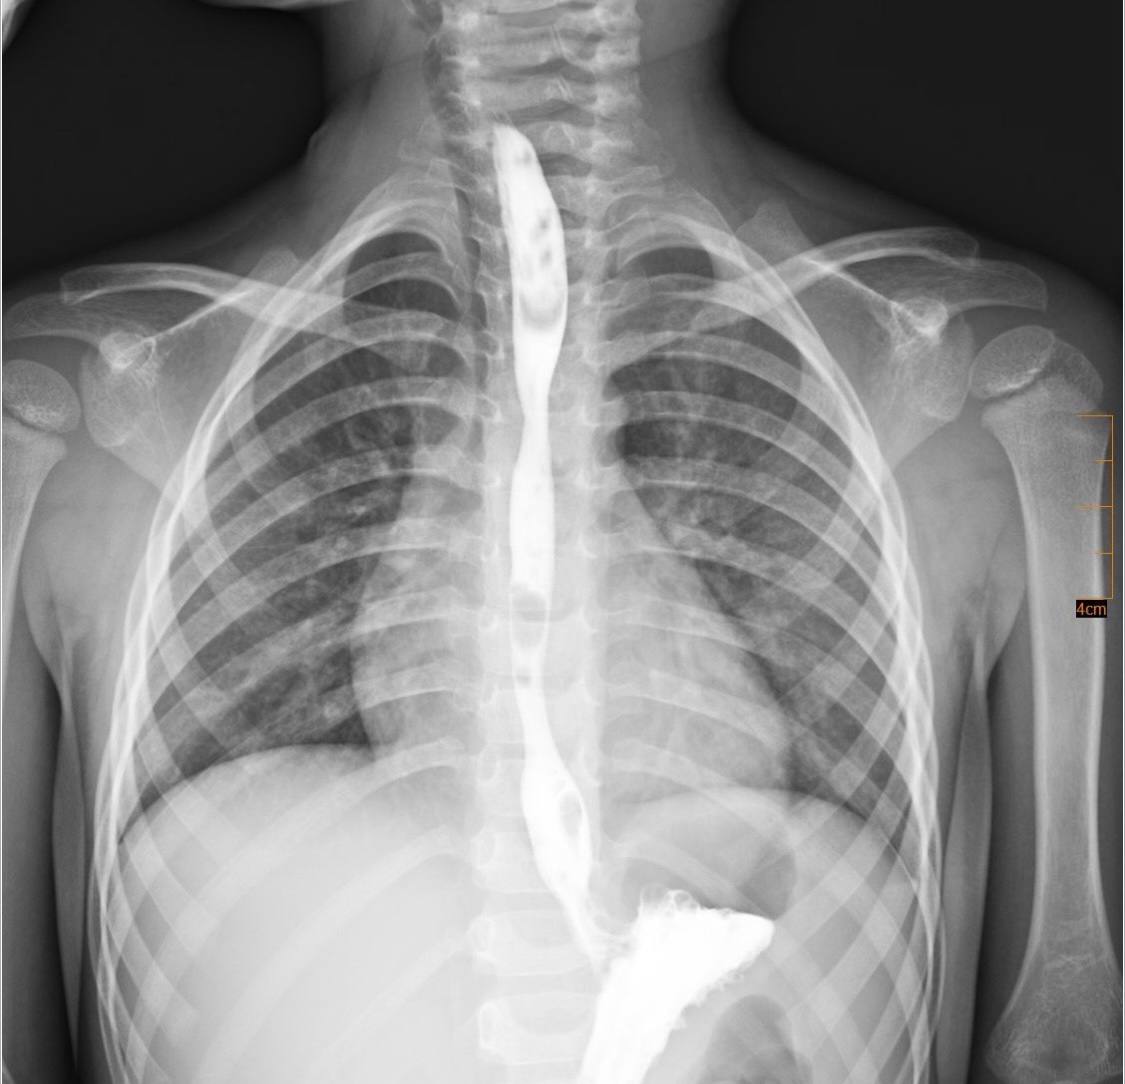

Згодом сформувався критичний стеноз стравоходу — значне звуження просвіту, яке повністю унеможливлювало прийом їжі через рот. Після обговорення мультидисциплінарною командою було ухвалено рішення провести серію балонних дилатацій — малоінвазивних ендоскопічних процедур, під час яких звужену ділянку поступово розширювали спеціальним балоном без виконання розрізів.